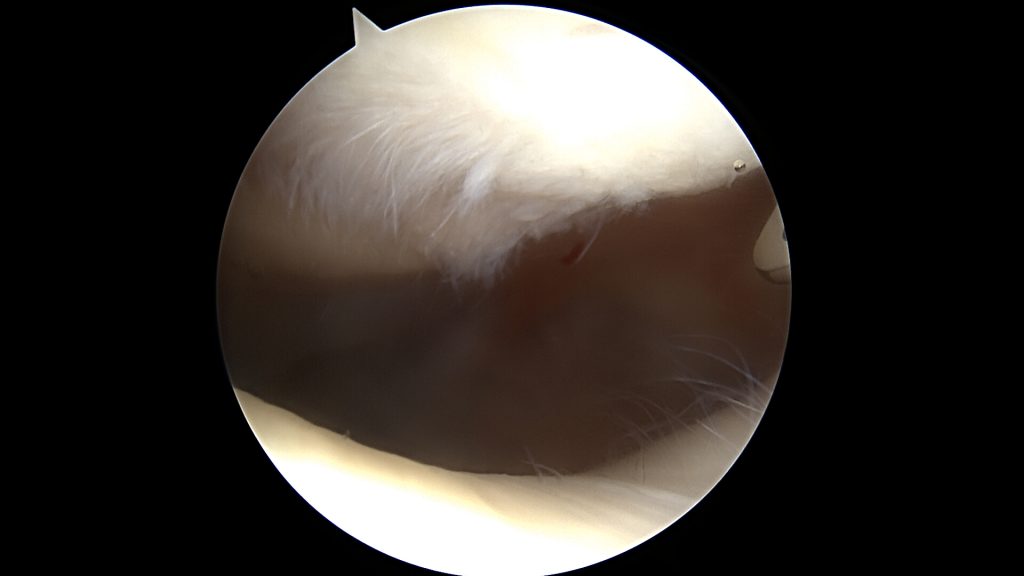

Uszkodzenia trzeciego i czwartego stopnia najczęściej wymagają leczenia operacyjnego. Same w sobie dają większe dolegliwości. Pozostawienie ich bez zaopatrzenia chirurgicznego może skończyć postępem oraz powiększaniem się uszkodzeń zarówno samej chrząstki jak i innych struktur w stawie. Leczenie zachowawcze w tych przypadkach nie przynosi oczekiwanych rezultatów.

Powierzchnie uszkodzenia trzeciego stopnia wyrównuje się mechanicznie, aby rozpulchnione fragmenty chrząstki nie stanowiły powierzchni ciernej.